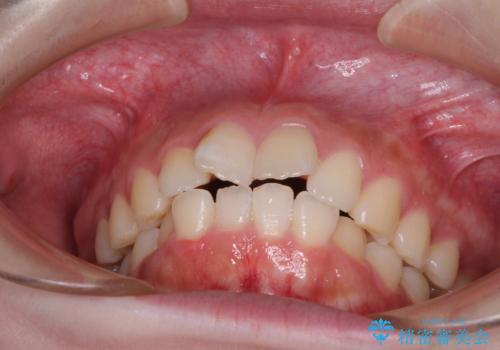

前歯のデコボコをインビザラインできれいに整える

- 前歯のデコボコと上下の隙間を気にして来院された患者様です。

前歯の捻れを改善するとともに、口元が少しでも引っ込むように治療計画を立て、仕上げることができました。